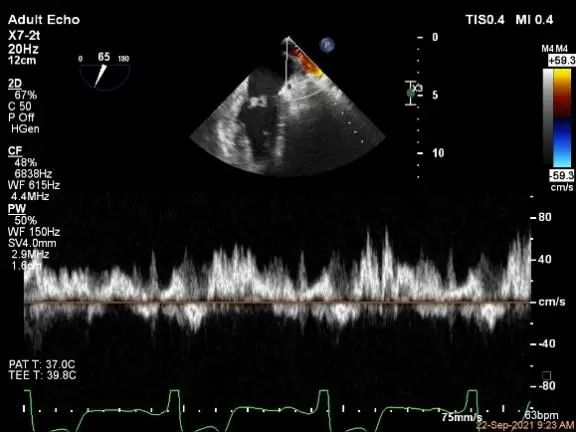

术中超声

P2区脱垂,宽14.8mm,Gap:3.3mm

3D-color,返流重度,3+级

麻醉状态下左肺静脉血流频谱

MVA:6.67cm²